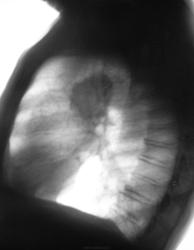

Зацепили при расшифровке флюорограмм, какие будут мнения уважаемые коллеги?

Была произведена обзорная рентгенограмма, было рекомендовано полное клиническое обследование, в плане проведения д/диагностики рекомендована также консультация фтизиатра.

Но, видать основания для тревоги не было. И, через год пациент был направлен на профилактическую флюорографию.

Пацинт стандартно был дообследован.

Однозначно была рекомендована консультация онколога.

Но..., прошел год и пациент был направлен на профилактическую флюорографию органов грудной клетки....